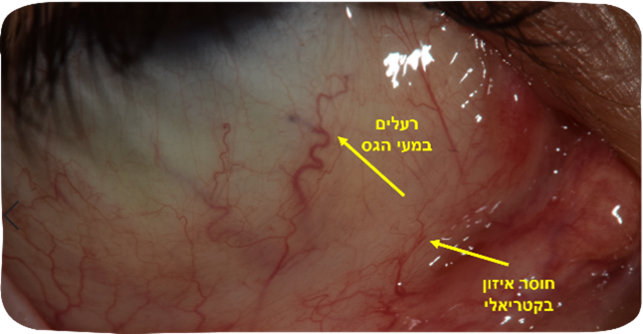

בצילום קשתית העין של מטופל שסבל במשך שנים ממיגרנות קשות התגלתה חולשה מרכזית במערכת העיכול. אותו מטופל סבל כבר גם מכיבים בתריסריון ובמעיים שהיו דלקתיים. פענוח הממצאים בלובן העין אצלו חשף גם חוסר איזון בקטריאלי, חומציות גבוהה, והצטברות רעלים במעי הגס ובסינוסים. בהתאם לכך הותאם לו טיפול שכלל איזון בקטריאלי של מערכת העיכול, הורדת חומציות ושיקום הריריות שנפגעו, ניקוז הסינוסים וריענון הכבד. ואכן תוך כמה שבועות כאבי הראש פחתו והוא הפסיק לצרוך אופטלגין – תרופה אותה לקח במינונים גבוהים. עם המשך הטיפול ירדה תדירות המיגרנות מהתקף יומיומי משתק לכאב בעוצמה נמוכה פעם בכמה שבועות שעבר ללא צורך בתרופות.